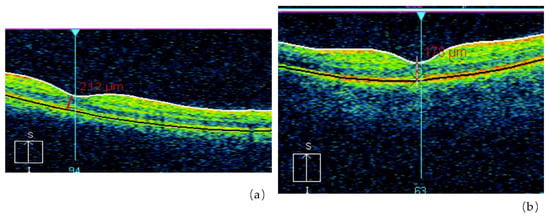

- Fedirko, P.; Babenko, T.; Kolosynska, O.; Dorichevska, R.; Garkava, N.; Grek, L.; Vasylenko, V.; Masiuk, S. Morphometric parameters of retinal macular zone in reconvalescents of acute radiation sickness (in remote period). Probl. Radiac. Med. Radiobiol. 2018, 23, 481–489. [Google Scholar] [CrossRef]